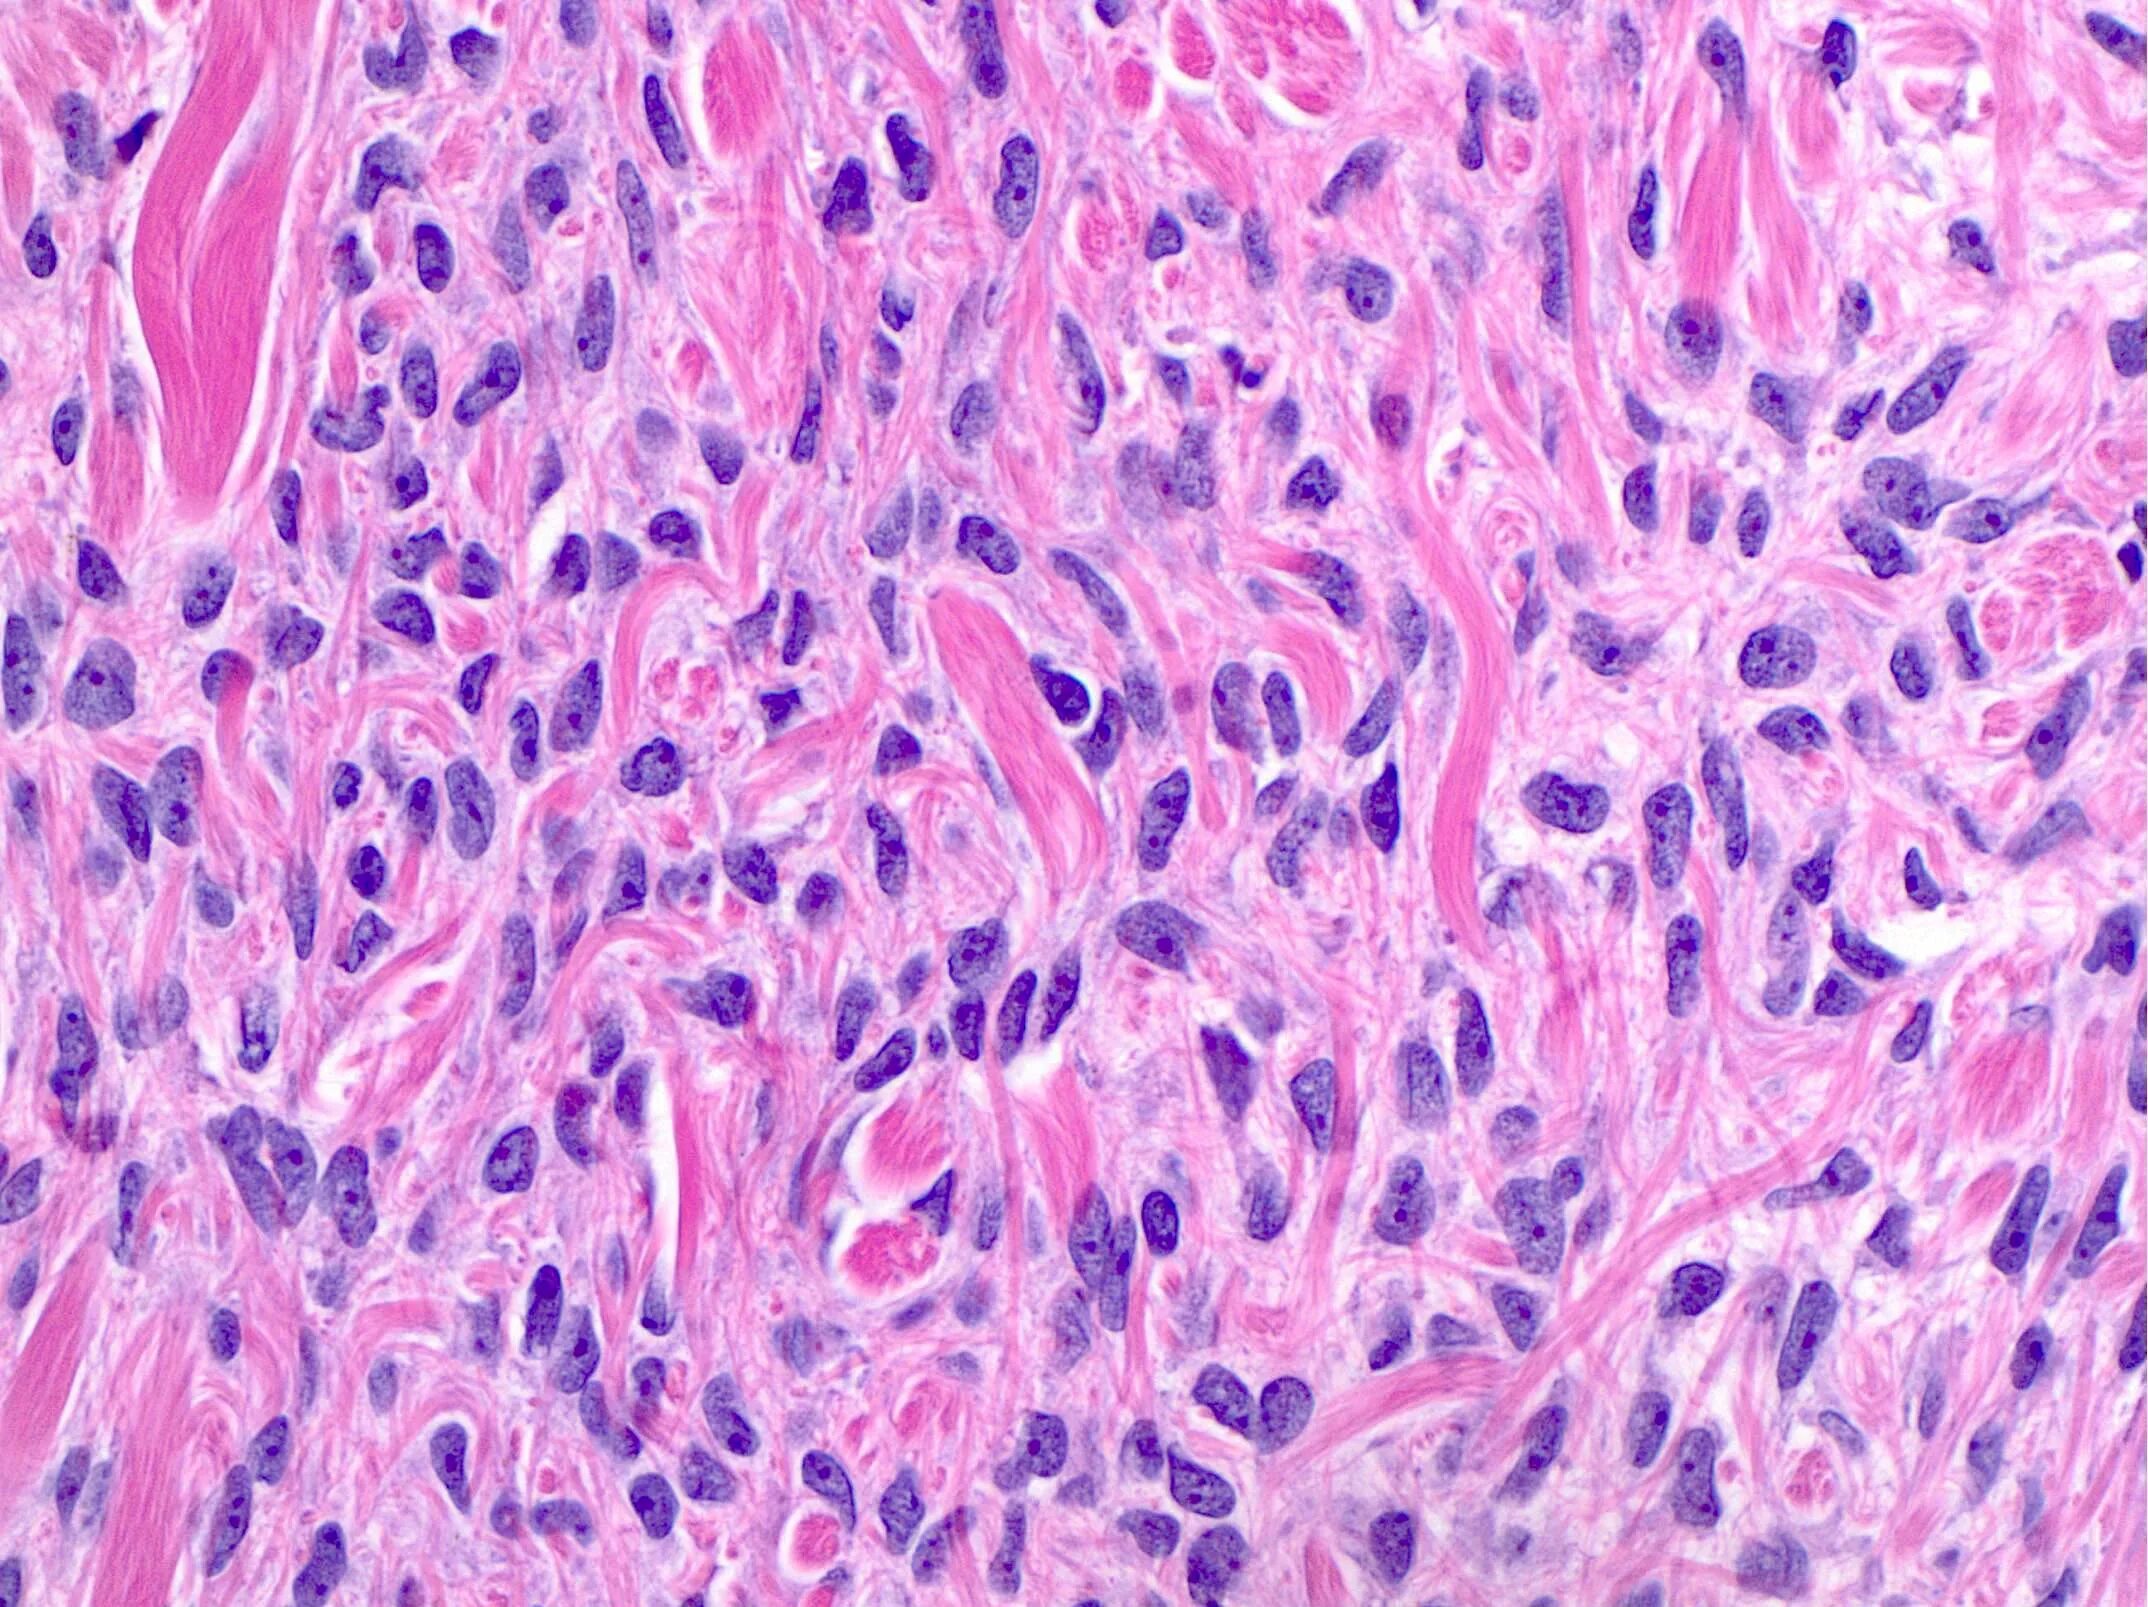

Фиброматоз мягких